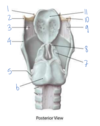

Which muscle is labeled by #1?

What is its action?

Aryepiglottic muscle

Pulls the epiglottis posteriorly to help close the larynx - opposes the thyroepiglottic muscle

(Restricts the opening like a purse string, but doesn’t close it completely)

Which structure is labeled by #5?

What is its action?

Cricothyroid muscle

Phonation - Tilts the thyroid forward to tense the vocal cords -> higher pitches

Innervated by the external laryngeal nerve

Which structure is labeled by #7?

Cricothyroid ligament

Which structure is labeled by #7?

Cricoid cartilage

(Also #9)

Which muscle abducts the vocal cords to open the airway?

5 - posterior cricoarytenoid

Which structure is labeled by #3?

Lateral cricoarytenoid muscles

(Adduct/close the vocal cords)

Which structure is labeled by #5?

What is its action?

Posterior cricoarytenoid muscle

Abducts vocal cords -> opens airway

Which fold is labeled by #2?

Vestibular fold (aka false vocal fold)